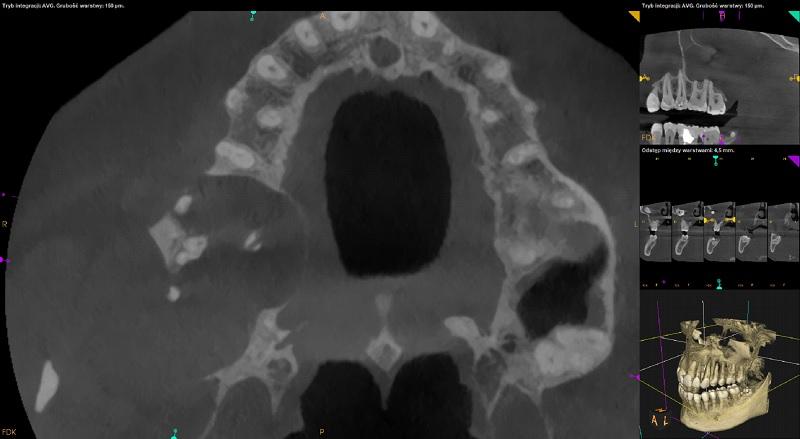

Rozległa zmiana w widocznym zakresie prawej zatoki szczękowej modelujące, uwypuklające, cienkie ograniczenia kostne zatoki z rozległą destrukcją bocznej ściany oraz dna zatoki w okolicy 18 (około 41mm x 29,5mm x 38,5mm). Rozdęcie zarysu wyrostka zębodołowego w okolicy 16-17 z destrukcja blaszek zbitych po stronie przedsionkowej i podniebiennej. Wierzchołki korzeni zębów 17,16 objęte zmianą – widoczna resorpcja wierzchołków korzeni. Zmiana wpukla się do przewodu nosowego środkowego prawego ograniczając jego drożność. Przemieszczony ząb 18 widoczny w części górnej zatoki przy ścianie przedniej. Możliwa torbiel zapalna, mucocele - do pilnej konsultacji laryngologicznej i chirurgicznej z ewentualnym poszerzeniem diagnostyki (np. w badaniu TK z kontrastem iv), ocena kliniczna i ew.biopsja.